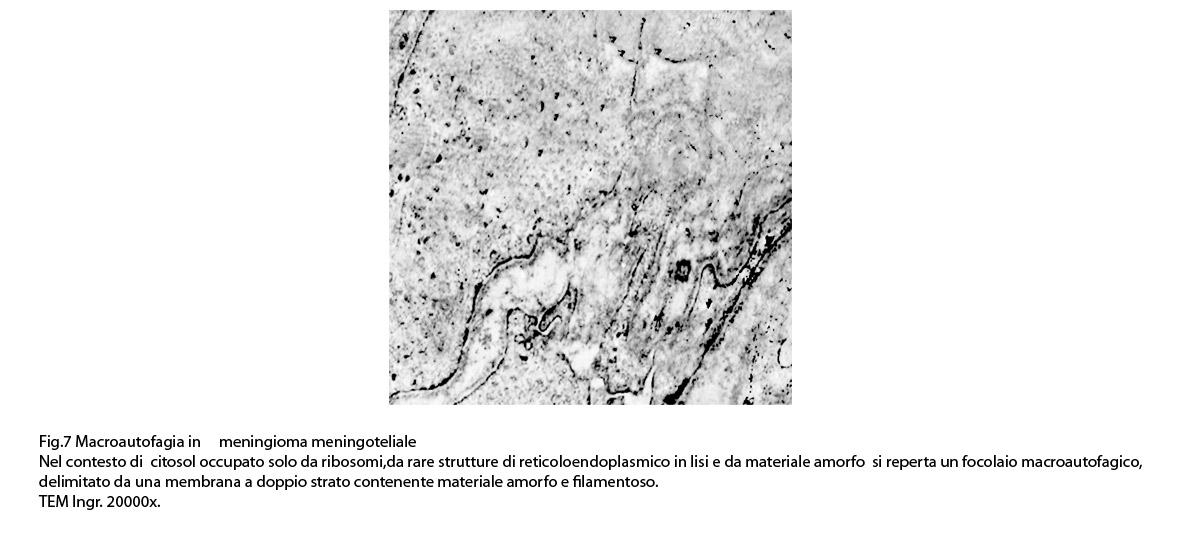

2) MACROAUTOFAGIA

La macroautofagia ,come sopra è stato fatto cenno,è un processo che si manifesta per stadi evolutivi; di questi, due sono, sul piano ultrastrutturale, diversi e sono indicati quali autofagosomi e auto lisosomi; pertanto la loro presentazione richiede i seguenti due distinti paragrafi:

2/a AUTOFAGOSOMA

I focolai di macroautofagia possono essere presenti in zone diverse del citoplasma. La loro microstruttura di base è costituita da una area vacuolare demarcata da una membrana a doppio strato; l’area cava è occupata per quote variabili da materiale amorfo,da aggregati filamentosi,da frammenti di organuli,da gruppi granulosi, il tutto in diversi stati di conservazione. Questi focolai macroautofagici appaiono come strutture avulse dalle mutevoli condizioni bio-morfologiche del citoplasma nel quale si sono formate. E’ frequente il riscontro di cellule di aspetto cribroso per la esistenza di micro vacuoli scavati nel citosol e per la dilatazione delle cisterne del reticolo endoplasmico contengano nel citosol una formazione macroautofagica occupata in parte da materiale amorfo e filamentoso.

Non mancano elementi cellulari,forniti di un citosol contenente solo ribosomi liberi, rare strutture reticolo endoplasmatiche in via di disgregazione e molto materiale amorfo, essere occupati da un focolaio di macroautofagia con aggregati di filamenti.